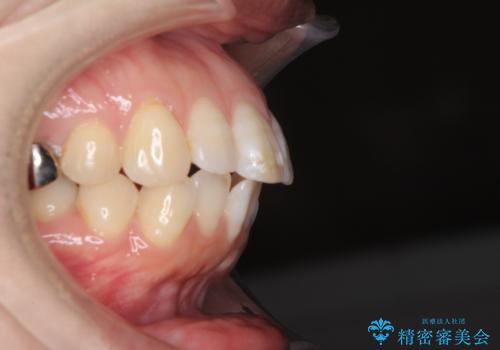

- 口元の閉じにくさと、前歯のでこぼこの歯並びを気にして来院された患者様です。

口元を積極的に引っ込めるために、上下左右の小臼歯計4本を抜歯することとしました。

セオリーでは第一小臼歯を抜歯しますが、上下右側は第二小臼歯に銀歯が装着されているため、第二小臼歯を抜歯することとしました。

上下正中を左右対称に揃えるため、アンカースクリューや補助装置を使用しながら口元を下げていくこととしました。